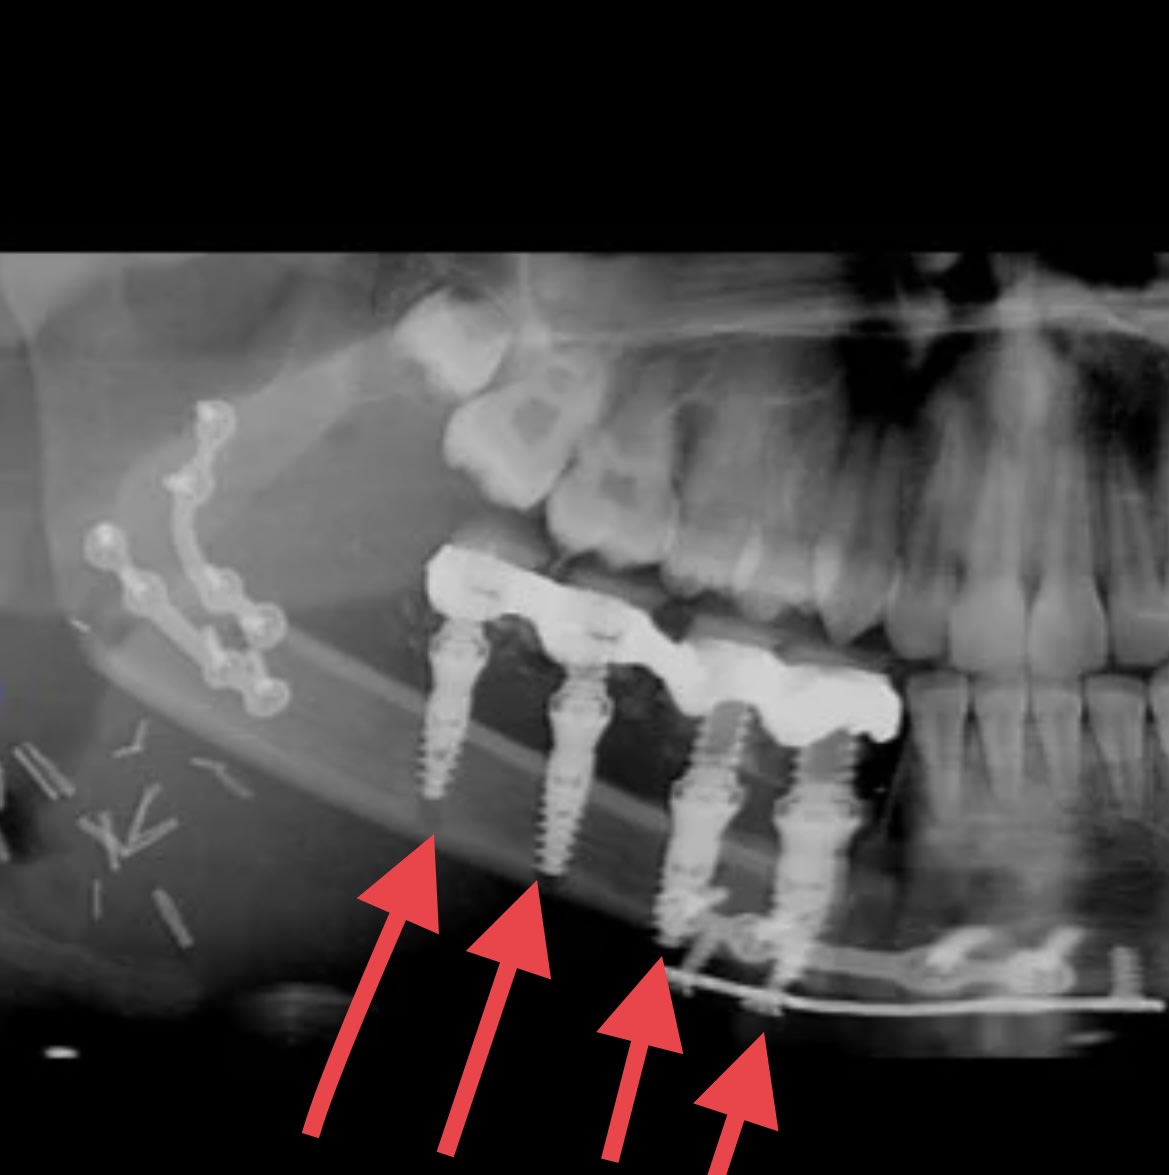

Stop bouboule, reprend le truc à la base. T'es partie sur affirmation d'hokusai :

"bin si tu trouves qu ils sont bien posés c est cool 👍

l implant le plus distal avec ces 5 spires en dehors de l os... chapeau l artiste.

une gestion de la profondeur de forage aux petits oignons..."..."t aurais du faire carriere chez pinder"

1 / Les spires c'est à l'apex > voila pourquoi la photo de la greffe montrant le coté où ces spires pourraient apparaitre

2/ Les spires des implants en mésial qui semblent perforer la corticale sur la pano ne le font pas en clinique et tu voudrais que je ne me pose pas de question ?

3 /si tu as une explication, je suis preneur parce que l'autre compte sur toi

C’est bien joli tout ça mais tu mens quand tu affirmes que les deux derniers implants sont ok.

Tu mens ou tu n’y connais rien, pas d’autre choix.

Tu mens et tu n’y connais rien ?

C’est une illusion d’optique due à la différence de taille des flèches !

C’est bien connu, et le rouge ne fait qu’augmenter l’illusion.